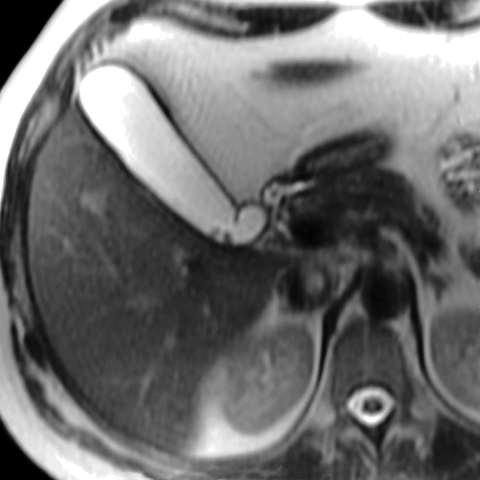

Cholelithiasis, Axial T2 weighted MRI